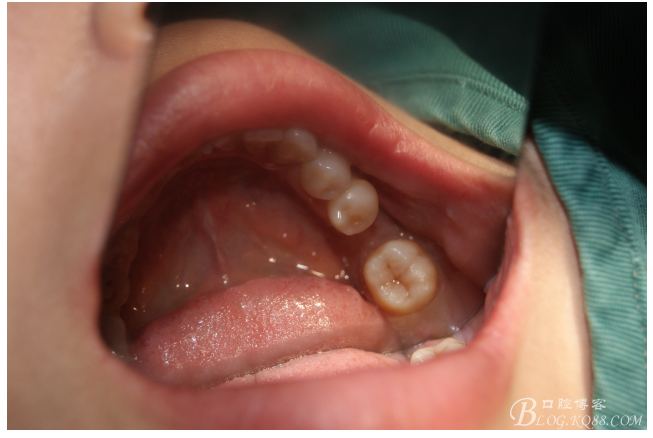

檢查:36.46缺失,36缺牙區(qū)近遠中間隙約3mm,46缺牙區(qū)間隙約0.5mm,37.47.48近中傾斜,48近中面齲壞達牙本質(zhì)淺層,37牙周探診4mm,47近中探診深度5-6mm,不松,口內(nèi)照片及CT片如下:

口內(nèi)照片